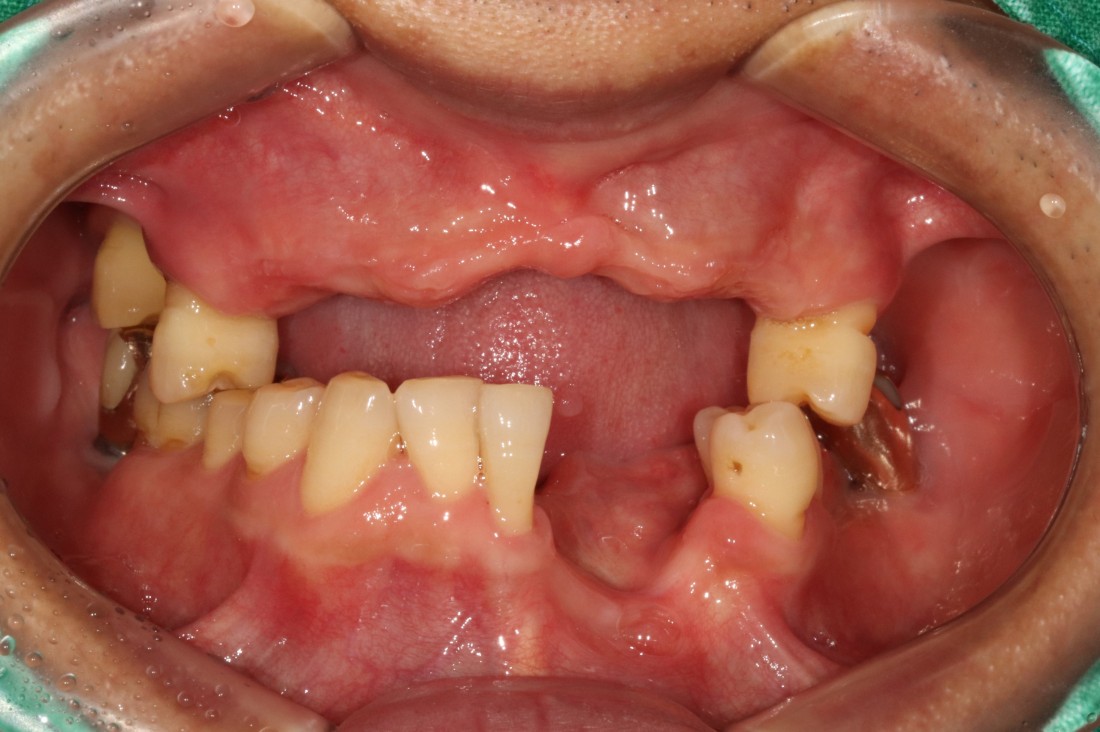

전남광주 임플란트 치과에서는

디지털가이드 임플란트 수술방법으로

한 번에 8개 이상의 임플란트를

심을 수 있습니다.

위, 아래 전체 임플란트를

단 두 번의 수술만으로 완성할 수 있어

임플란트 치과에 자주 내원하지 않으셔도 되고,

붓기 / 출혈 / 통증도 적기 때문에

빠른 회복을 기대할 수 있습니다.